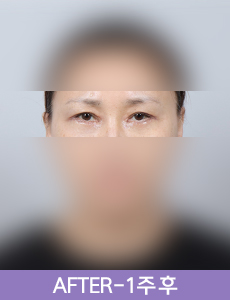

실제 환자 전후

확인하실 수 있습니다.얼굴전체,이마,눈/여성/60대/수술리프팅,비수술 리프팅,리프팅부스터리팅L리프팅+심부볼제거+베네핏부스터+보톡스+필러